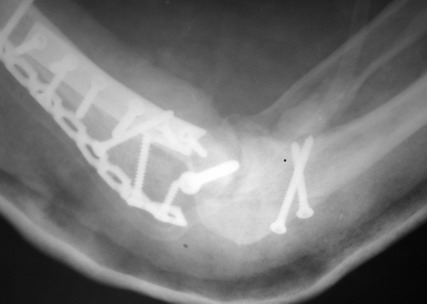

Солидарен с мнением обоих Александров (Челнокова и Рыкова): точную репозицию такого перелома вряд ли удастся выполнить закрыто. Даже во время открытого вмешательства это сделать непросто. Неслучайно предложен костно-пластический доступ с временным отсечением локтевого отростка. И по методу фиксации согласен с Александром Челноковым: 2 пластины. В качестве примера привожу рентгенограммы одного из наших пациентов с аналогичным повреждением.